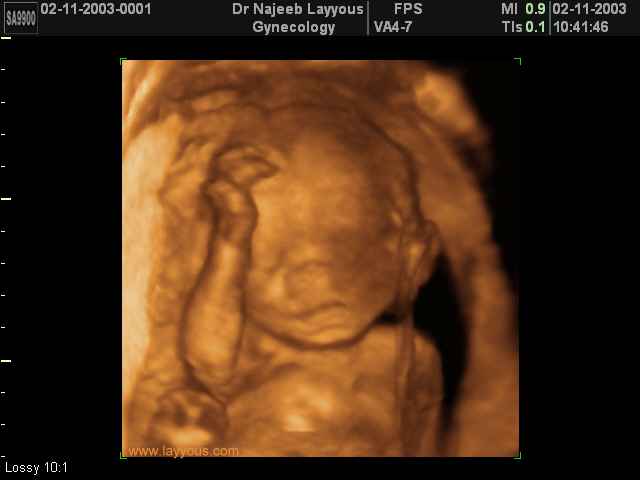

- Fetal Behavior Ultrasound Photos

Ultrasound Photos in 3D showing Fetal Behavior Inside the uterus | Dr N Layyous